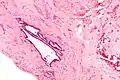

It is characterized by cysts with tubal-type epithelium (e.g. ciliated epithelium) surrounded by a fibrous stroma. It is not often associated with hemorrhage.

Endosalpingiosis is occasionally found in lymph nodes, and may be misinterpreted as an adenocarcinoma metastasis.[6]